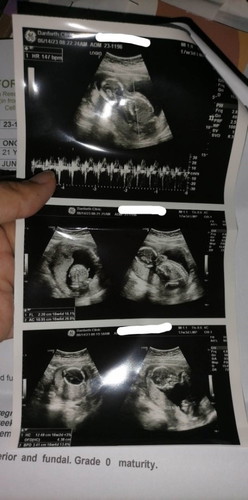

16 weeks and 4days

Hi po mga mommy ask ko lang po kung normal lang puba heartbeat ni baby at iikot pa kaya sya thankyou po sa sasagot #FTM

Normal po lahat. Iikot pa yan si baby kasi maluwag pa sa loob. Breech din baby ko nun 5-6months, ngayon cephalic na 8mos hopefully di na siya umikot kasi ilang weeks nlang

Normal lang. and wag magworry sa position ni baby unless nasa 37weeks ka na. dahil umiikot ikot pa ang baby sa ganyang weeks. hanggat di pa nagteterm.